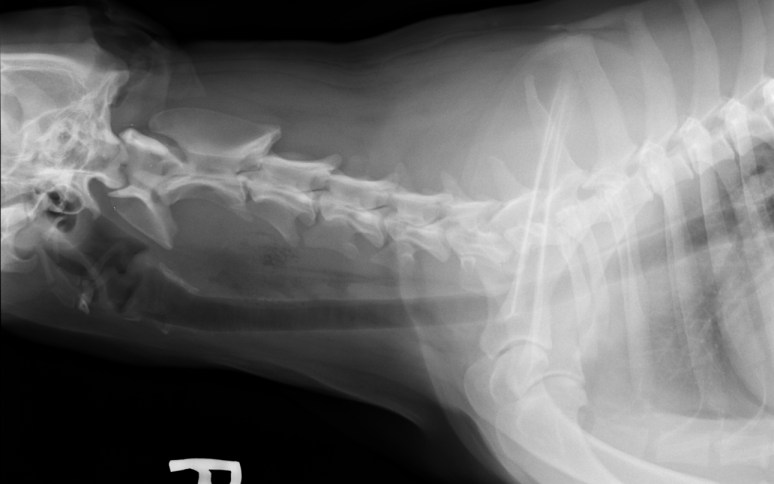

Cas intriguant 3 – Réponse

Sur les radiographies, nous avions noté d’abord un déplacement ventral et vers la droite de la trachée cervicale, de même qu’une zone hétérogène dans les tissus mous ventraux à la colonne vertébrale, associée à la présence de multiples petites bulles de gaz. Sur la VD, une opacité minérale était aussi visible médialement à l’épaule gauche, mais celle-ci s’est avérée non significative.

Robert faisait remarquer la forme bizarre de l’atlas (C1). En fait, cette forme est attribuée à la rotation axiale de la colonne qui déplace les ailes dorsalement/ventralement (têtes de flèches ci-bas) et qui libère le processus odontoïde (dens) qui devient alors très bien défini. Cette vue latérale alors que la tête est légèrement tournée, est fort utile lorsqu’on cherche à éliminer la possibilité de fracture ou d’hypoplasie de la dens (qui entraîne une luxation atlanto-axiale). Le problème chez ce chien se trouve ailleurs… portez attention aux tissus mous ventralement à la colonne vertébrale… Je vous raconte la suite d’ici quelques jours.

Cas intriguant 3 – Diantre, que se passe-t-il avec ce chien ?

Signalement: Labrador de 2 ans, femelle stérilisée.

Histoire clinique: Dysphagie, douleur au cou, boiterie de non appui MTG, parésie MPs pire a gauche. Lésion suspectée au niveau cervical caudal latéralisée à gauche.